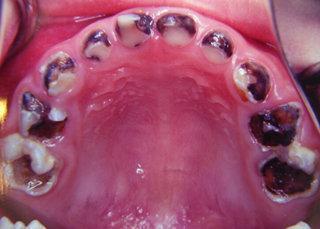

虫牙,医学上称为龋齿,是一种常见的口腔疾病。根据《中国口腔健康报告》显示,我国成年人龋齿患病率高达90%以上。即使是明星,也难逃虫牙的困扰。